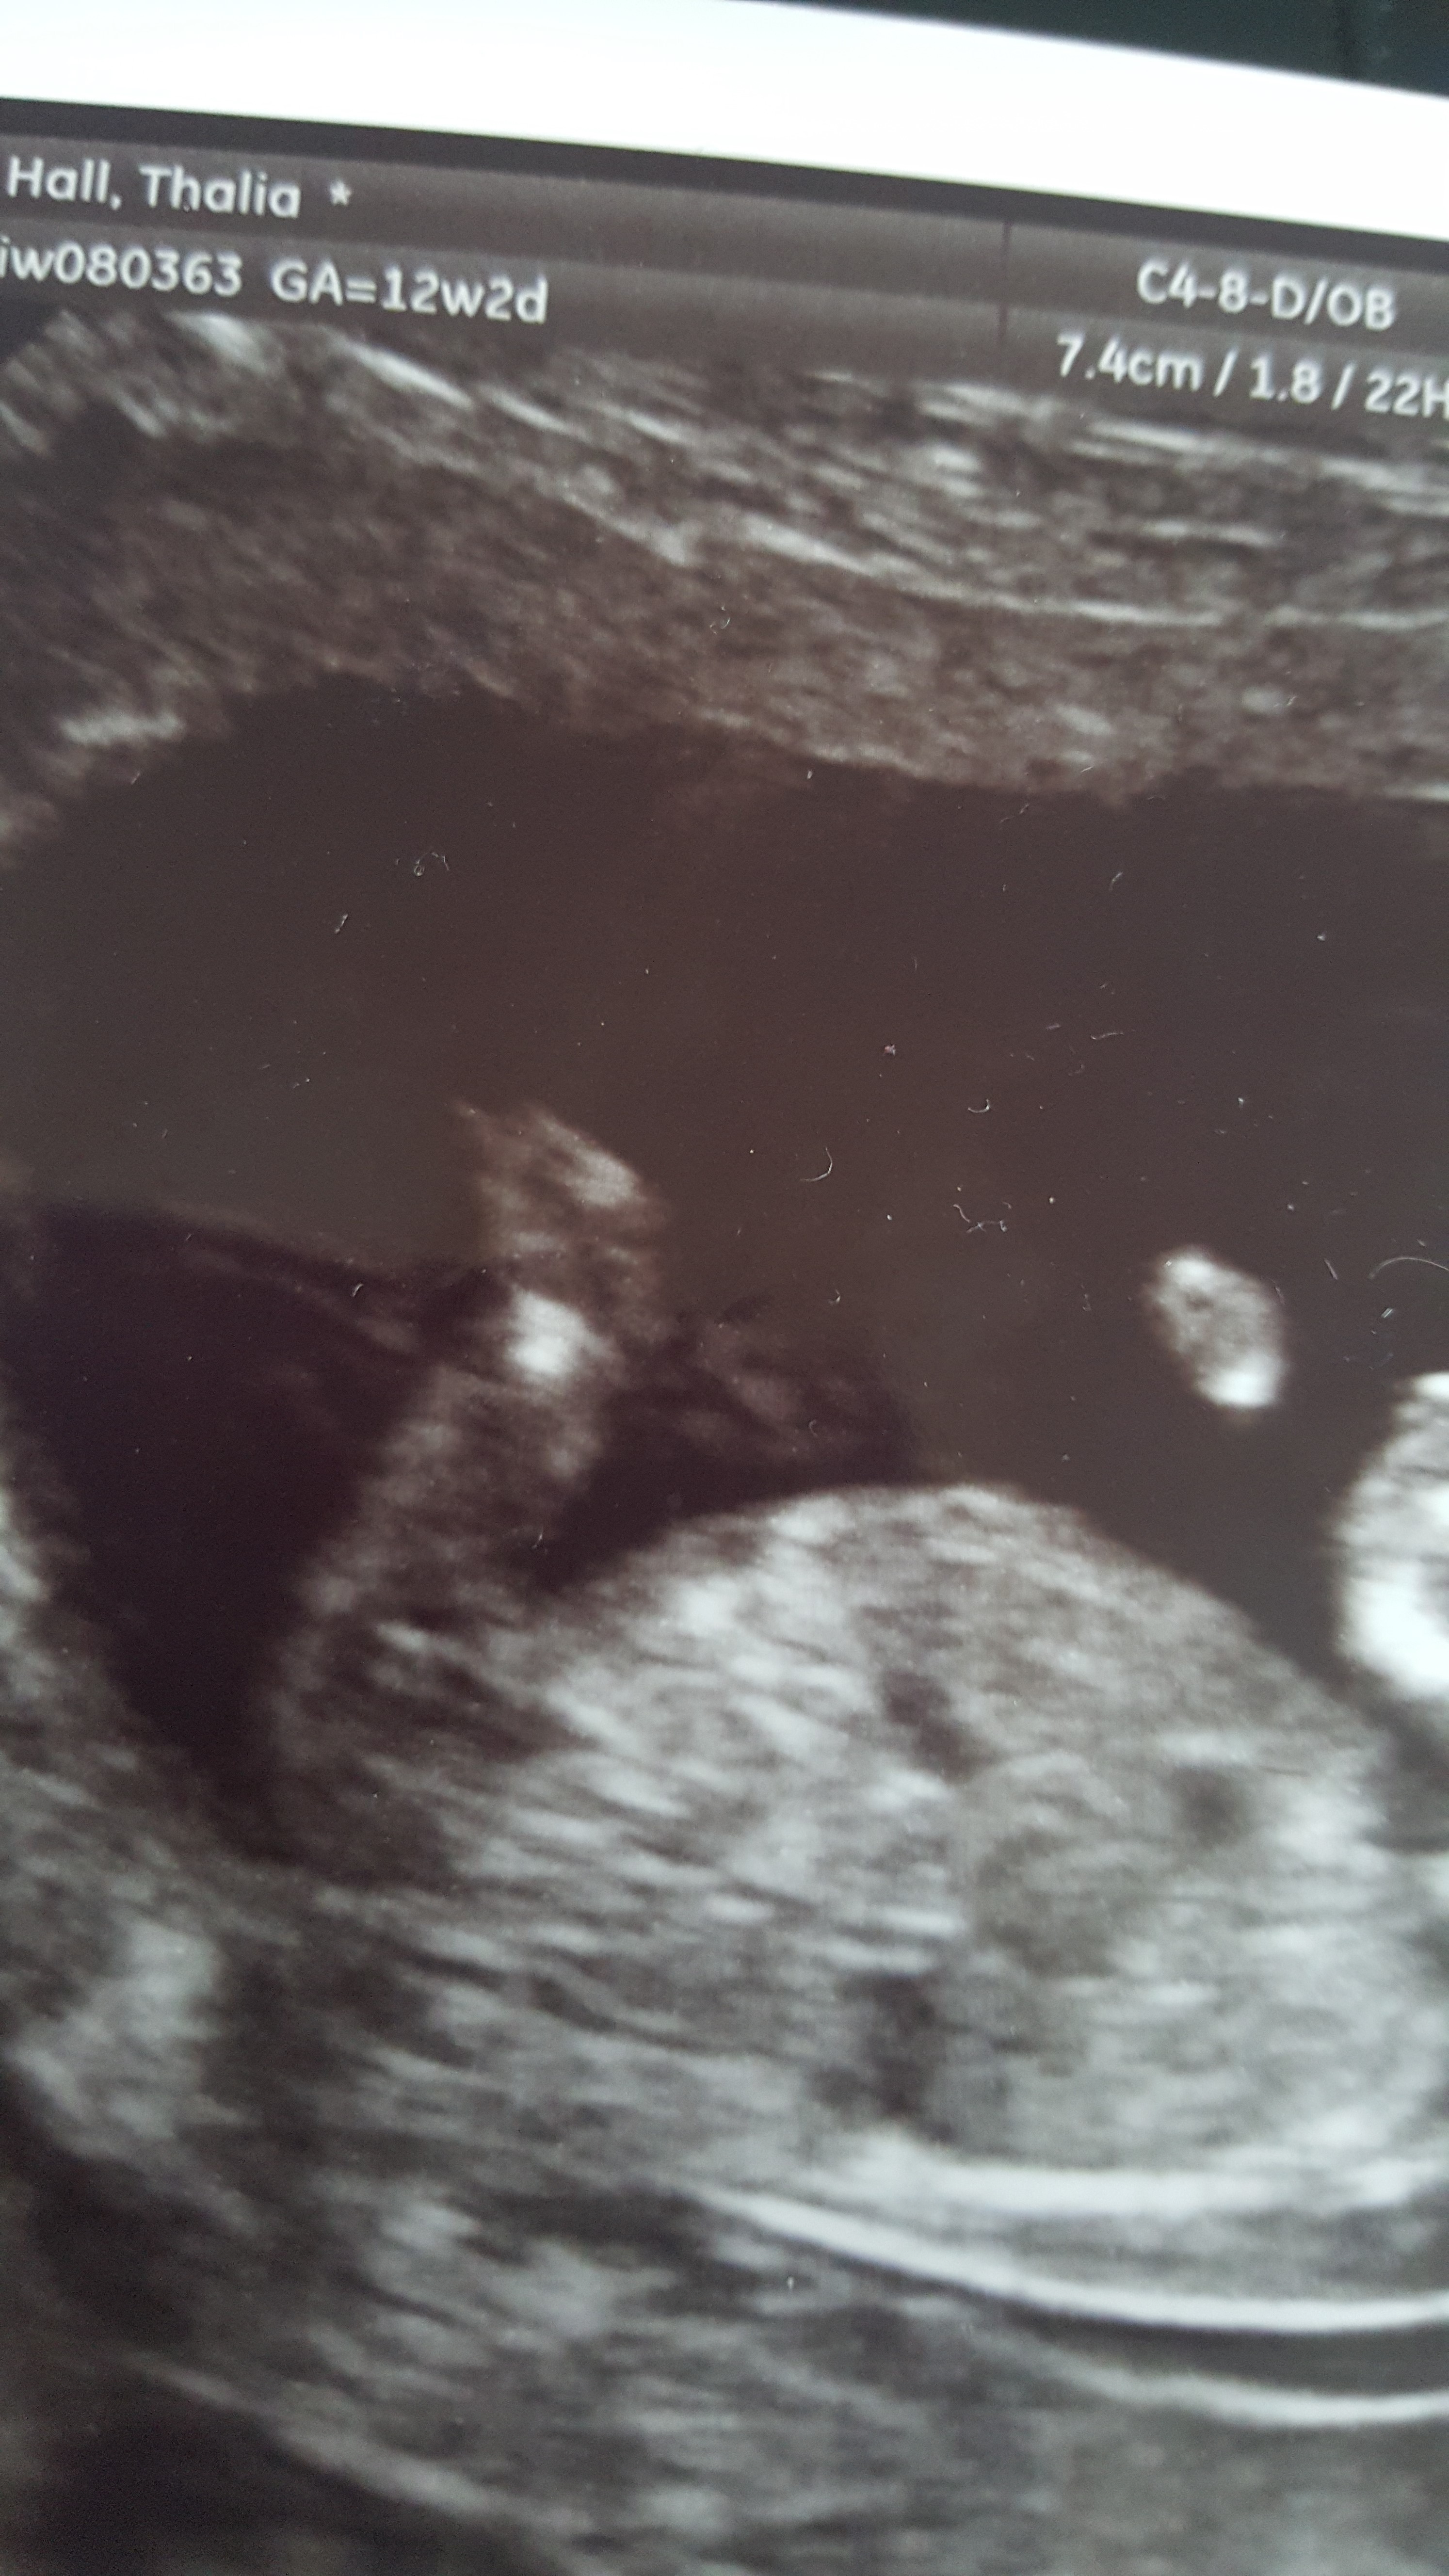

Hey everyone just had my 12 week scan and not sure if I can see the nub or not? Attachment 26804

Anyone have any ideas boy or girl?

There might be a vague girly nub there, but I'm not sure. FX!

not sure if that is the nub but would say gilr if it was x

Thinking maybe girl too if that's the nub I see

Girl guess